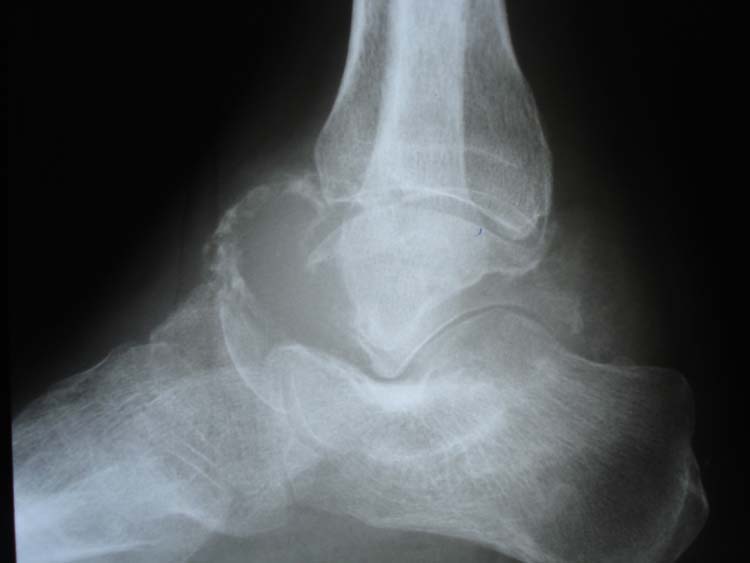

From www.bonetumor.org

A lesion in the talus of an 88 year old woman with 2 previous tumors Talus Bone Tumor Bone tumors of the talus are even rarer,. Bone tumors of the talus are even. Results revealed 75 cases of talar lesions. Radiologists as well as orthopaedic surgeons need to be. The talus is a rare location for tumors; Radiologists as well as orthopaedic surgeons need to be aware of such. Osseous neoplasms of the foot are uncommon, accounting for. Talus Bone Tumor.